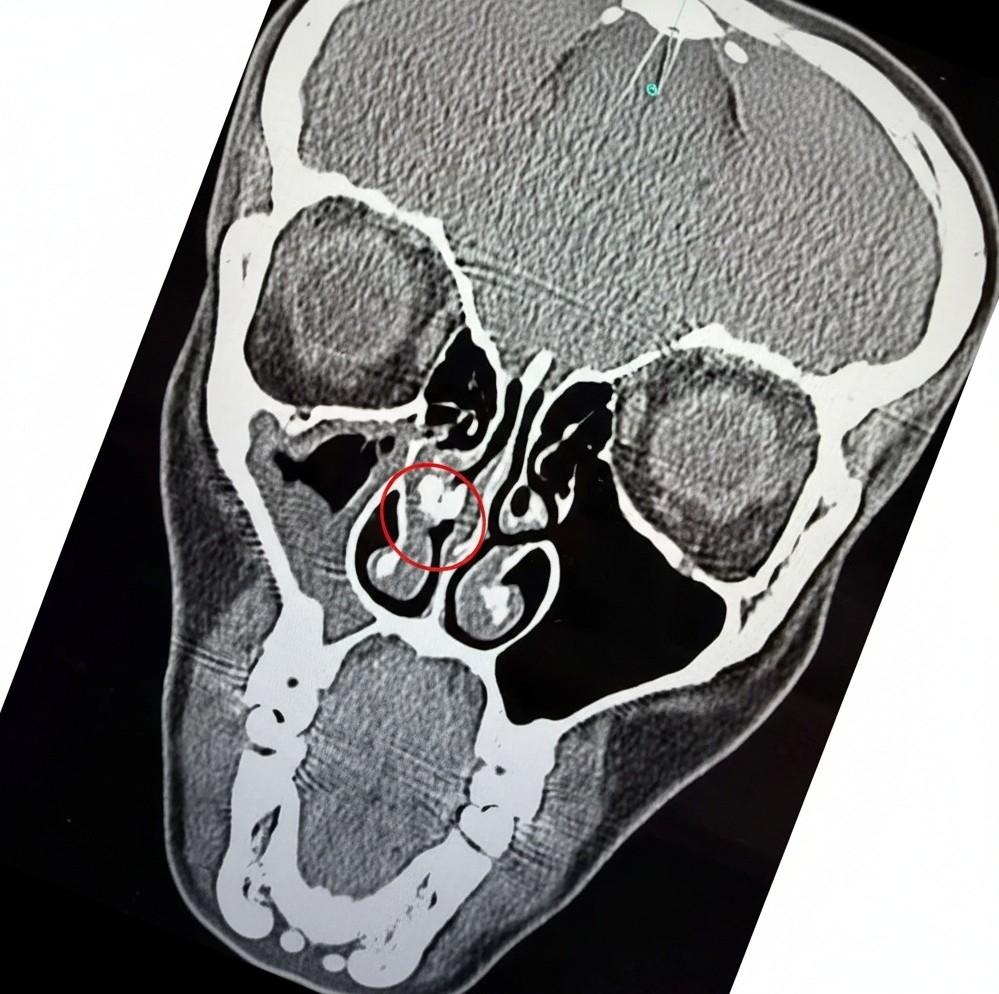

Медицинское обследование, включая компьютерную томографию, наконец-то пролило свет на загадку. Снимок, показавший инородное тело внутри носовой полости, стал первым шагом к разгадке. Каково же было удивление врачей и самой Кенделы, когда после несложной процедуры из ее носа был извлечен… комок скотча. Да, обычная липкая лента, которая десятилетиями находилась внутри ее дыхательных путей.